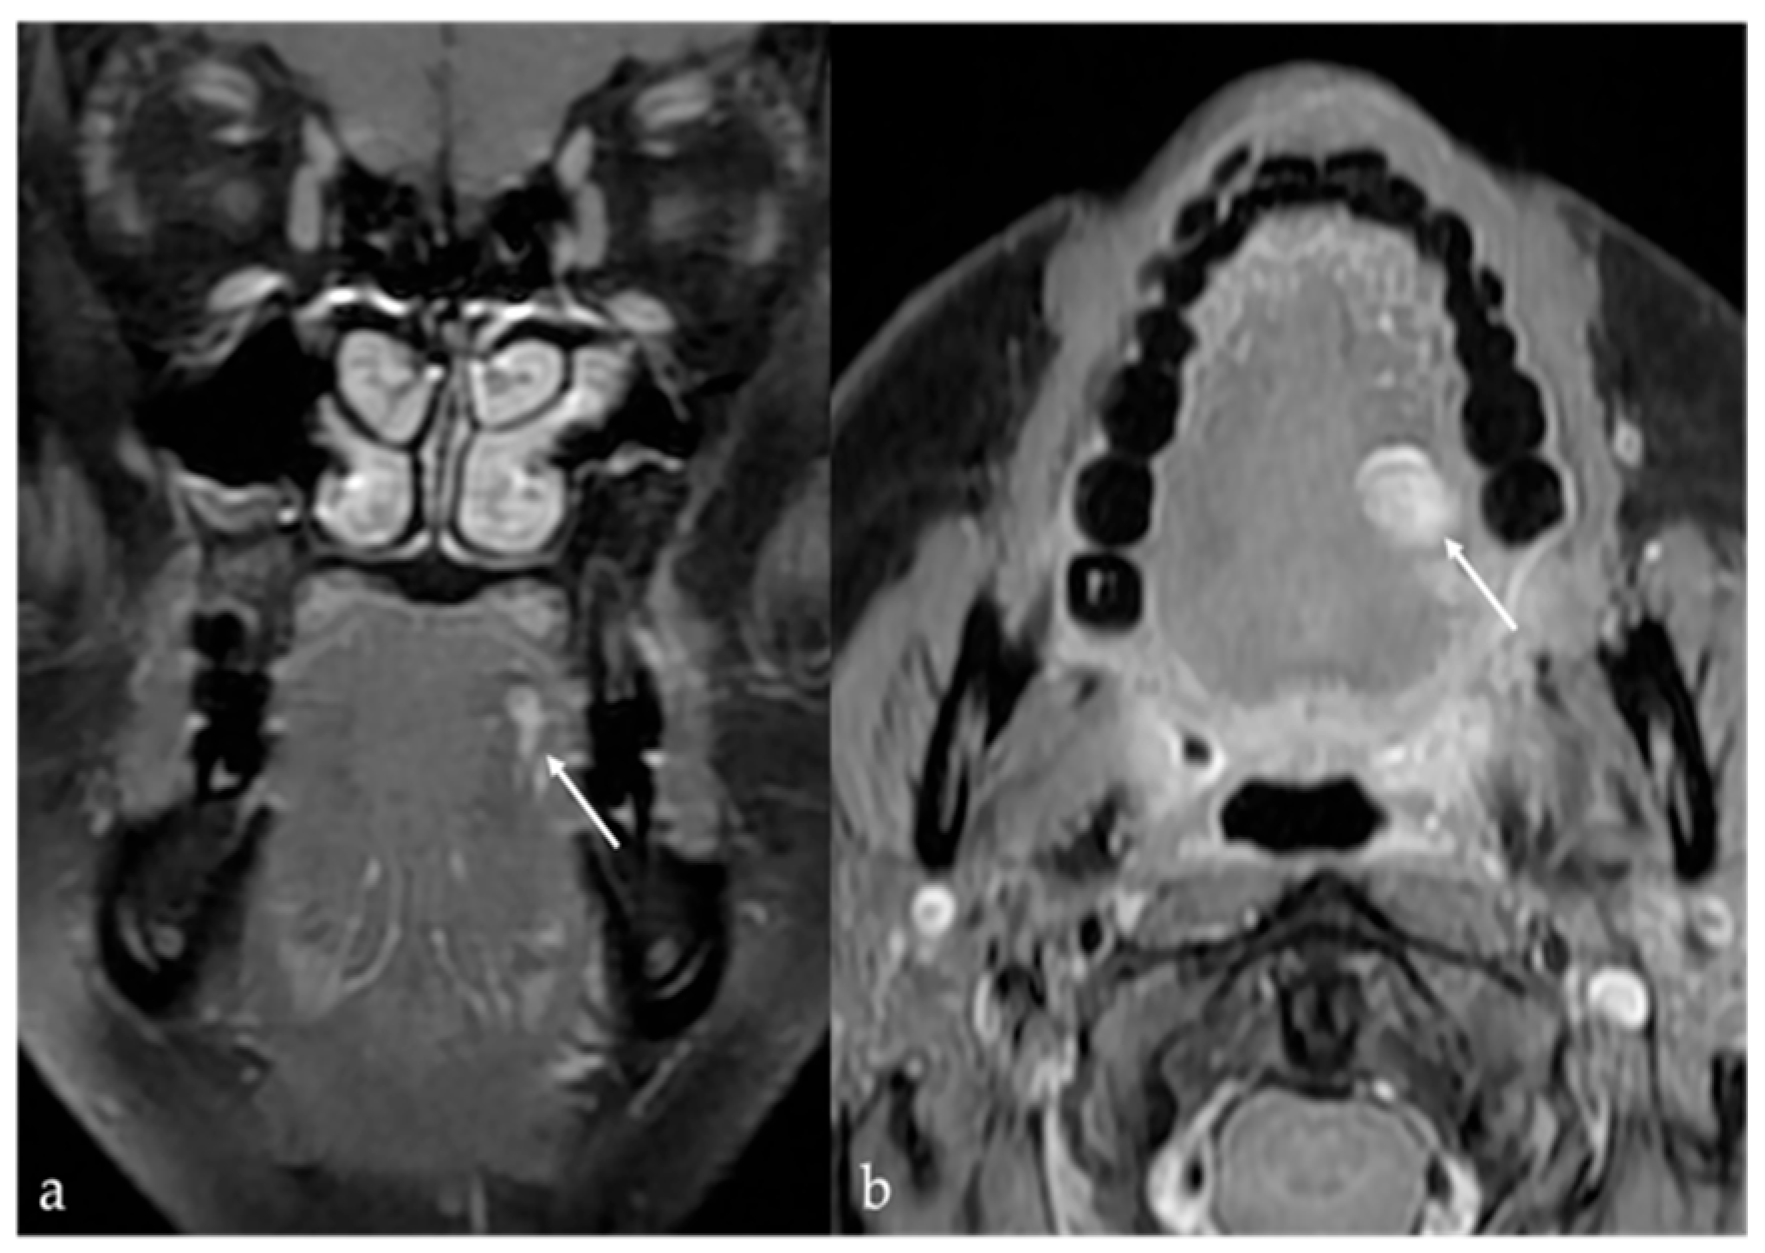

5.1. Venous Malformations

| Venous malformation [1,9] | CT: phleboliths MRI: high T2 SI, +CE | Other vascular malformations, schwannoma, dermoid cysts |